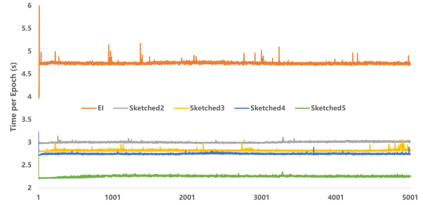

Equivariant Imaging (EI) regularization has become the de-facto technique for unsupervised training of deep imaging networks, without any need of ground-truth data. Observing that the EI-based unsupervised training paradigm currently has significant computational redundancy leading to inefficiency in high-dimensional applications, we propose a sketched EI regularization which leverages the randomized sketching techniques for acceleration. We then extend our sketched EI regularization to develop an accelerated deep internal learning framework -- Sketched Equivariant Deep Image Prior (Sk.EI-DIP), which can be efficiently applied for single-image and task-adapted reconstruction. Our numerical study on X-ray CT image reconstruction tasks demonstrate that our approach can achieve order-of-magnitude computational acceleration over standard EI-based counterpart in single-input setting, and network adaptation at test time.